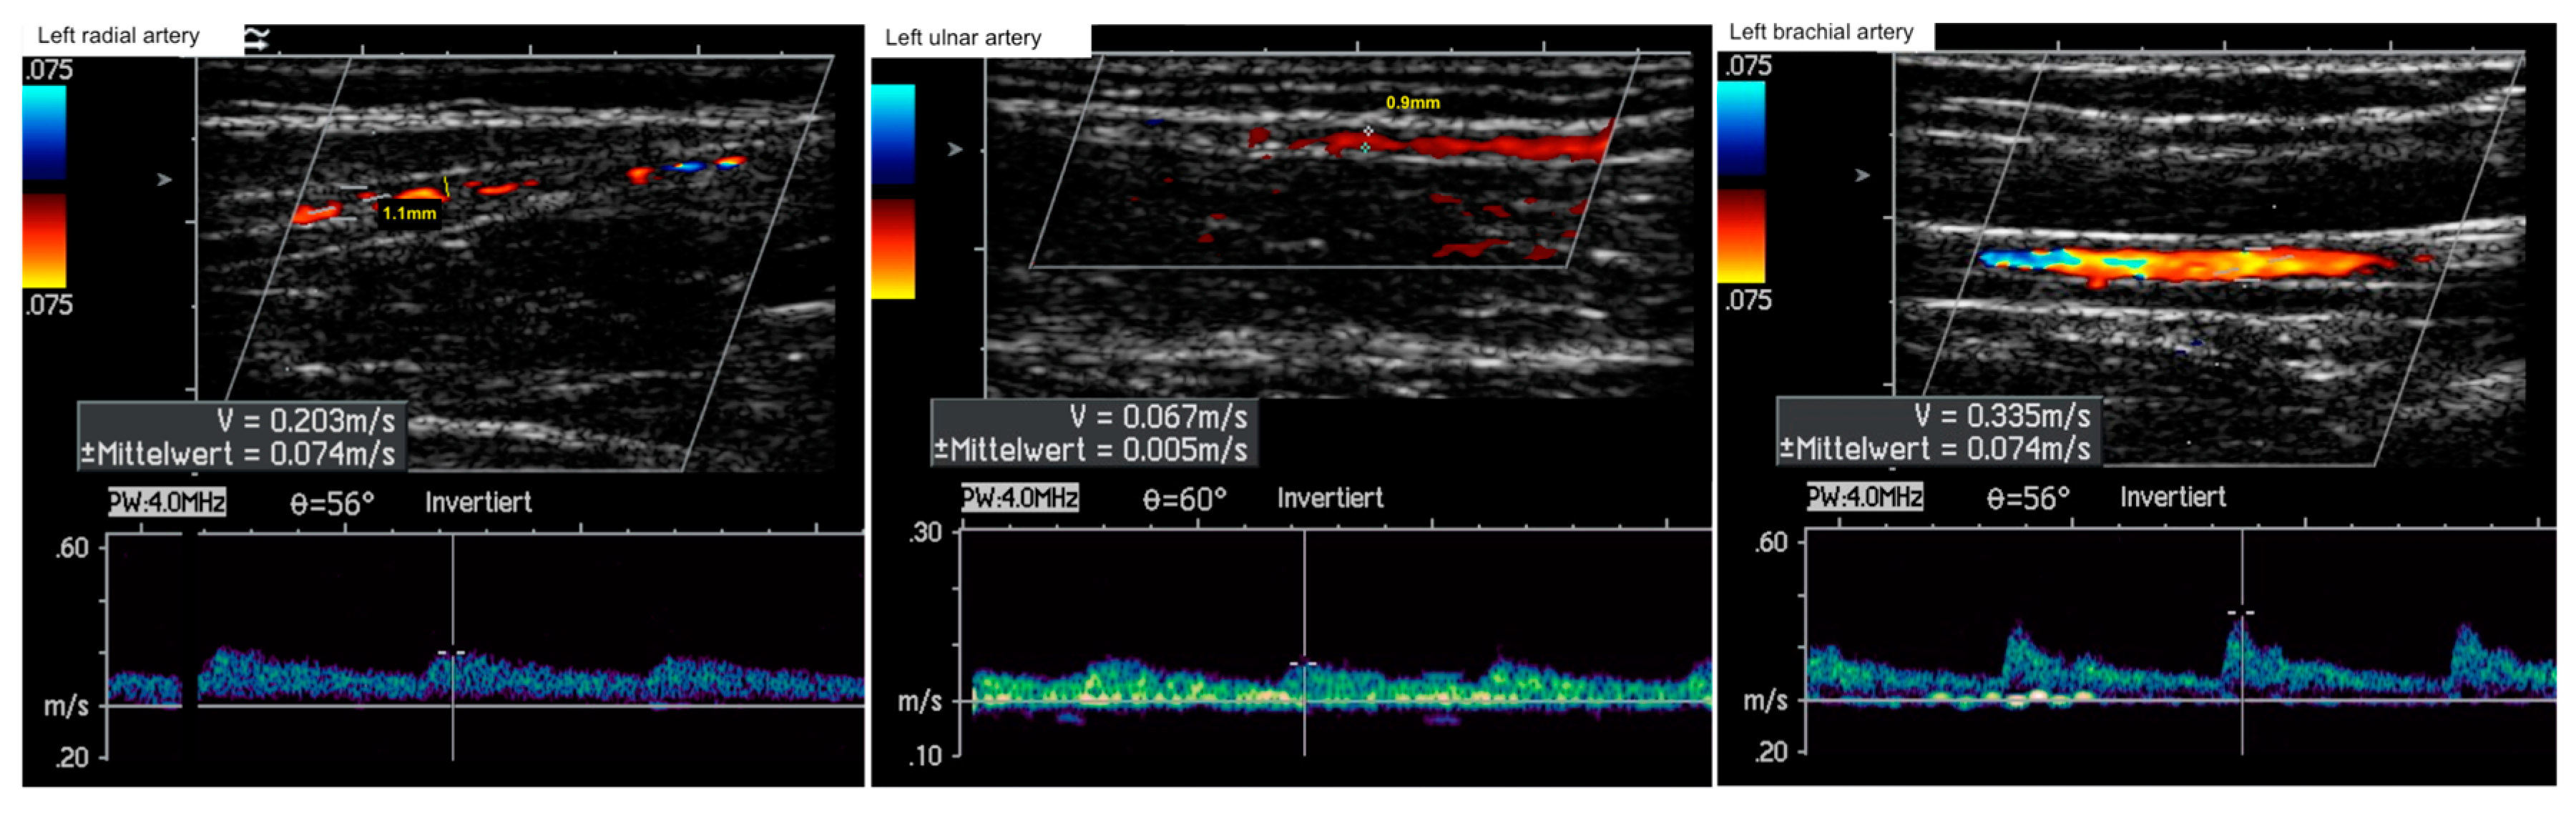

3.1. Routine Medical and Clinical Diagnostics